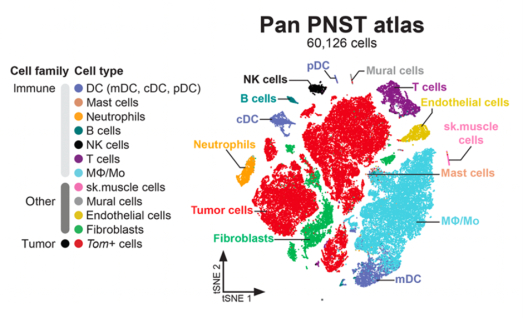

The article “Glial-to-mesenchymal transition of tumor Schwann cells drives the genetic burden in MPNSTs from neurofibromatosis type 1 mouse model” by Radomska KJ, Onfroy A, Lecerf L, Job B, Beaude A, Sesma Sanz L, El Jalkh T, Thieffry D, Charnay P, Wolkenstein P, Ortonne N, Coulpier F, and Topilko P. was published in Science Advances, 2025 Nov 12, Vol 11, Issue 45, DOI: 10.1126/sciadv.adt9210

This work reconstructs the natural history of malignant peripheral nerve sheath tumors, identifies the glial-to-malignant transition as a key driver, and highlights SOX9 as an actionable therapeutic target.